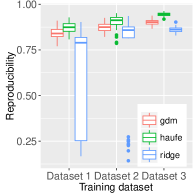

Multi-site study

To assess the predictive performance of the compared methods in a multi-site setting, we used the Schizophrenia dataset that comprises data from three sites. All models had their respective parameters cross-validated while training in one site before making predictions in the other two sites. Each training involved using of the site samples to allow for resampling the training sets 100 times to yield a distribution. The reproducibility across the resampled sets was measured using the inner product between model parameters. The multi-site prediction and reproducibility results are visualized in figure 3.

In five out of six cross-site prediction settings, GDM outperformed all compared methods in terms accuracy. Also, GDM had higher reproducibility than ridge regression, while having slightly lower reproducibility than the generative procedure in Haufe et al. (2014).